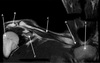

3

Q

What is letter A?

A

CORACOID PROCESS

How well did you know this?

1

Not at all

2

4

5

Perfectly

What is letter B?

DELTOID MUSCLE